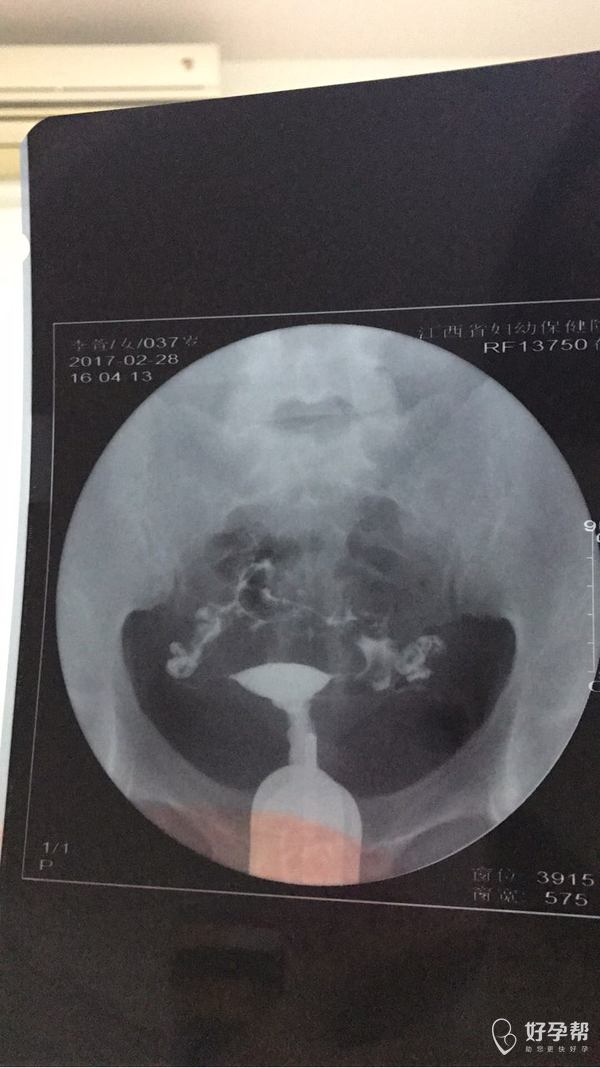

备孕二胎一年多,检查项目如下均均正常。2月28日造影通而不畅,试孕未果。06年生育一胎,08年手术人流一次,人流后上爱母环。之后由于经血过多引起贫血,11年取环,一直套套避孕。二胎放开后尝试一直未成功。想咨询是不是只能?后中药调理

好孕几率大吗?不是很想尝试试管这条路......